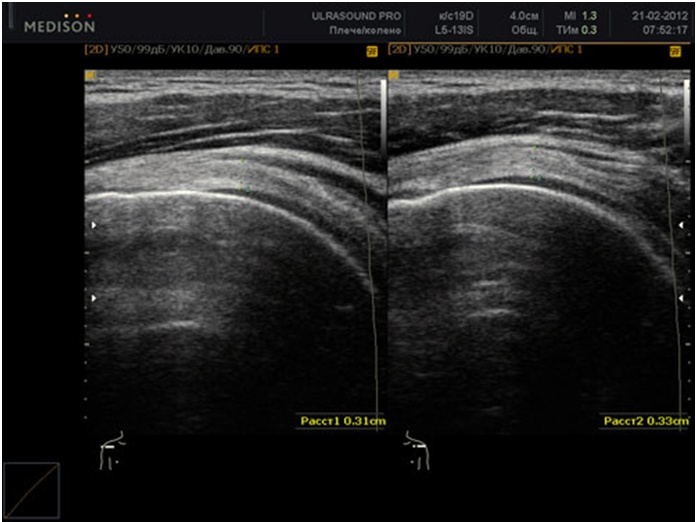

Пациент ложится на кушетку, обнажив нижнюю часть живота и спины. Тазобедренный сустав окружен различными тканями, поэтому исследование проводится в четырех плоскостях:

Передняя плоскость

Пациент лежит на спине, ноги вытянуты. Датчик перемещается по бедру. Исследование в этой плоскости позволяет оценить часть головки бедра, подвздошную кость, лимфатические узлы, мышцы паховой области и связки.

Латеральная плоскость

Пациент располагается на боку, а врач обследует верхнюю область. В этой позиции становятся видимыми аномалии в развитии большой берцовой кости и большого вертела бедренной кости.

После исследования органа во всех четырех плоскостях врач интерпретирует полученные данные. Травматолог получает важную информацию для оценки состояния следующих структур:

- подвздошной кости;

- гиалинового хряща;

- синовиальной суставной капсулы;

- головки бедренной кости;

- окружающих сухожилий и связок.